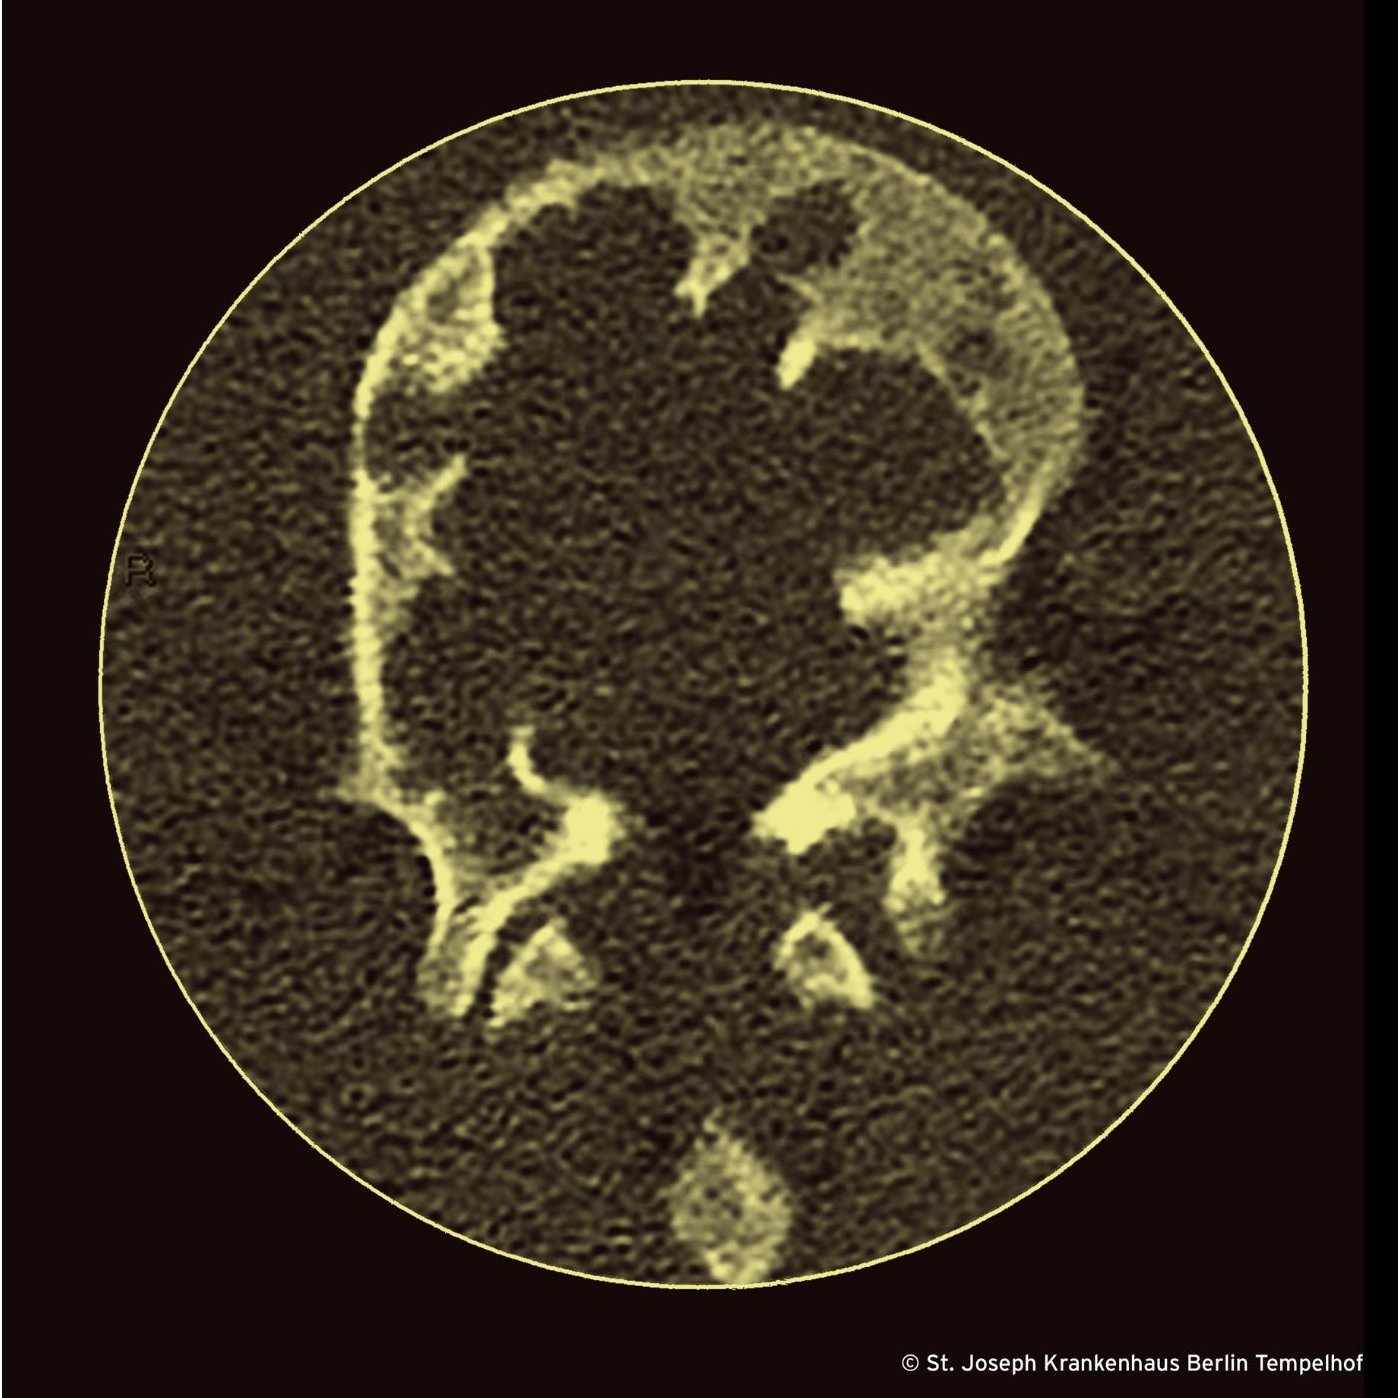

Dieser Befund veranlasste uns, die Bildgebung durchzuführen, aus der wir das Titelbild dieses Infektoskops gemacht haben. Es zeigt Destruktionen im Wirbelkörper und im ventralen Anteil der rechten Bogenwurzel von LWK4. Weil die Tuberkulose immer eine gute Differentialdiagnose ist, ergänzten wir die Diagnostik – trotz der unauffälligen Thoraxübersichtsaufnahme – um eine CT des Thorax und bronchoskopierten den Patienten aufgrund des Nachweises mehrerer TB-typischer pulmonaler Infiltrate. Die gewonnenen BAL Proben waren mikroskopisch negativ bezüglich säurefester Stäbchen, auch eine Mycobacterium tuberculosis-Komplex-PCR fiel negativ aus. Somit waren wir gezwungen, den Abszess zu punktieren. Im gewonnenen Material fanden die Mikrobiologinnen und Mikrobiologen mikroskopisch säurefeste Stäbchen, welche am nächsten Tag per PCR als eine Spezies des M. tuberculosis-Komplex identifiziert wurden. Erst drei Wochen später vermeldete die Mikrobiologie Wachstum von M. tuberculosis in der BAL Flüssigkeit.